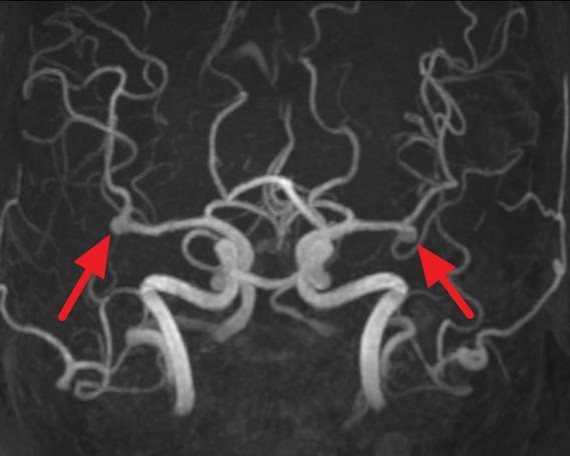

뇌동맥류는 뇌혈관이 꽈리처럼 부풀어 올라 있는 것을 뜻한다. 상대적으로 큰 직경의 뇌혈관에서 혈관벽을 이루는 탄성막의 결함이나 퇴행성 변화가 진행되면 혈관이 서서히 부풀게 되는데, 이를 뇌동맥류라고 한다.

뇌동맥류는 CT(컴퓨터단층촬영) 검사와 MRI(자기공명영상)를 이용해 10분만에 확인할 수 있다. 그래서 최근에는 조기 검진을 통해 뇌동맥류가 파열되기 전에 발견하는 사례가 늘고 있다.